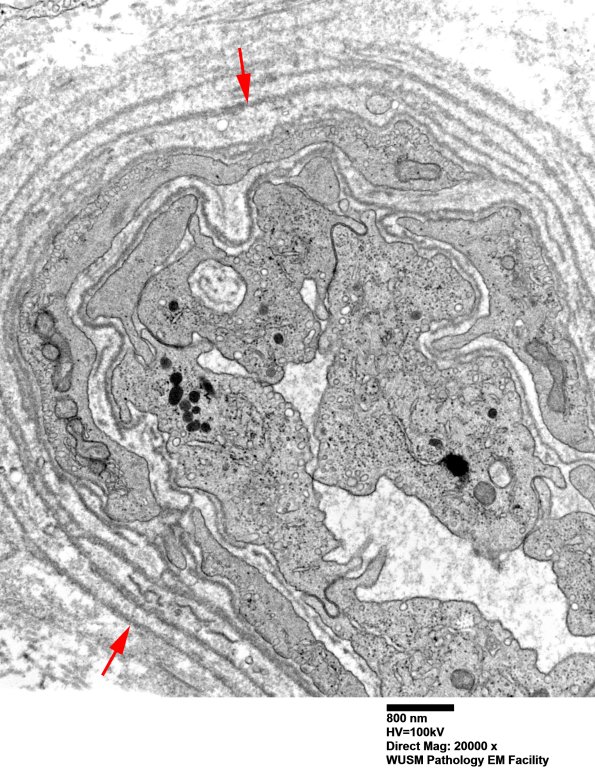

Washington University Experience | VASCULAR | Hypoxia-Ischemia, fetal-neonatal | White Matter | 16B2 (Case 16) HIEM EM018 - Copy copy

16B2 (Case 16) HIEM EM018 - Copy copy